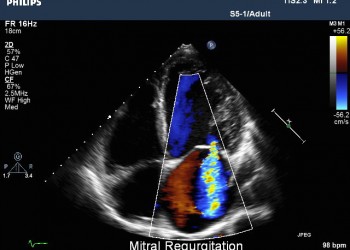

Insuficiența mitrală

Insuficien?a mitral? este datorat? absen?ei de etan?eitate a valvelor mitrale, sildenafil care produce în timpul sistolei ventriculare o regurgitare de sânge din ventriculul stâng în atriul stâng.

iv) Ecocardiografia: apreciază gradul regurgitării, permite măsurarea cavităţilor cardiace şi aprecierea presiunilor pulmonare.